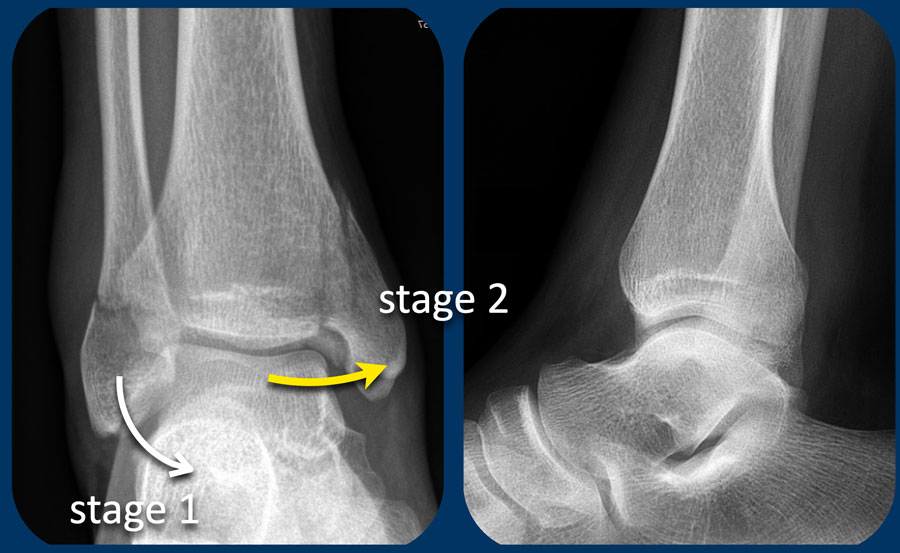

Hình bên trái là một ví dụ khác về gãy xương hai mắt cá không ổn định giai đoạn 2 Weber A.

Hình bên phải cho thấy đường gãy thẳng đứng của mắt cá trong (mũi tên). Đây luôn là giai đoạn 2 và không ổn định. Điều này có nghĩa là giai đoạn 1 đã xảy ra trước đó, vì cơ chế chấn thương luôn tuân theo trình tự nghiêm ngặt: giai đoạn 1 trước, sau đó mới đến giai đoạn 2.

Vòng ổn định bị phá vỡ ở hai vị trí (cuộn ảnh để xem).